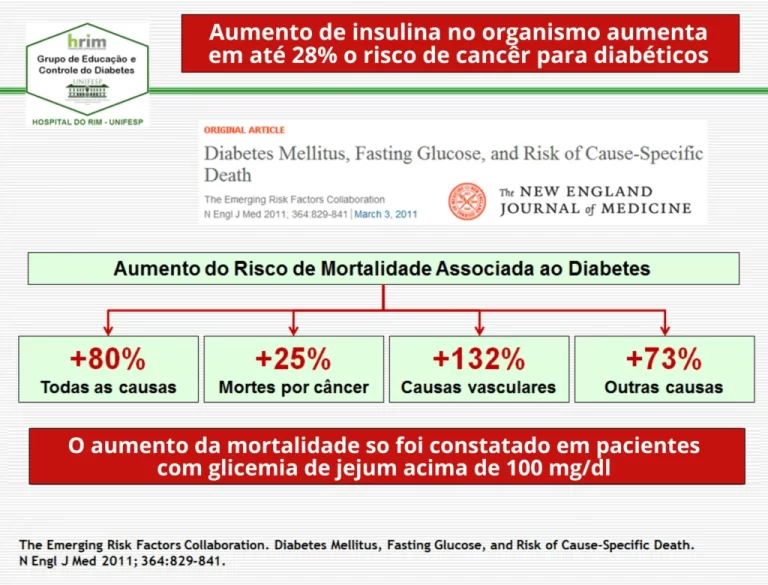

Os altos níveis de insulina destroem as células e fazem com que se dividam de forma anormal, levando à formação de tumores. Por isso, as estatísticas mostram que 25% dos diabéticos acabam desenvolvendo câncer.

Além disso, o excesso de insulina faz com que o sangue mais denso circule com dificuldade, bloqueando rapidamente os vasos sanguíneos com colesterol.

Isso leva ao aumento da pressão arterial. É por isso que 98% dos diabéticos sofrem com hipertensão e uma série de outros problemas no coração e na circulação.